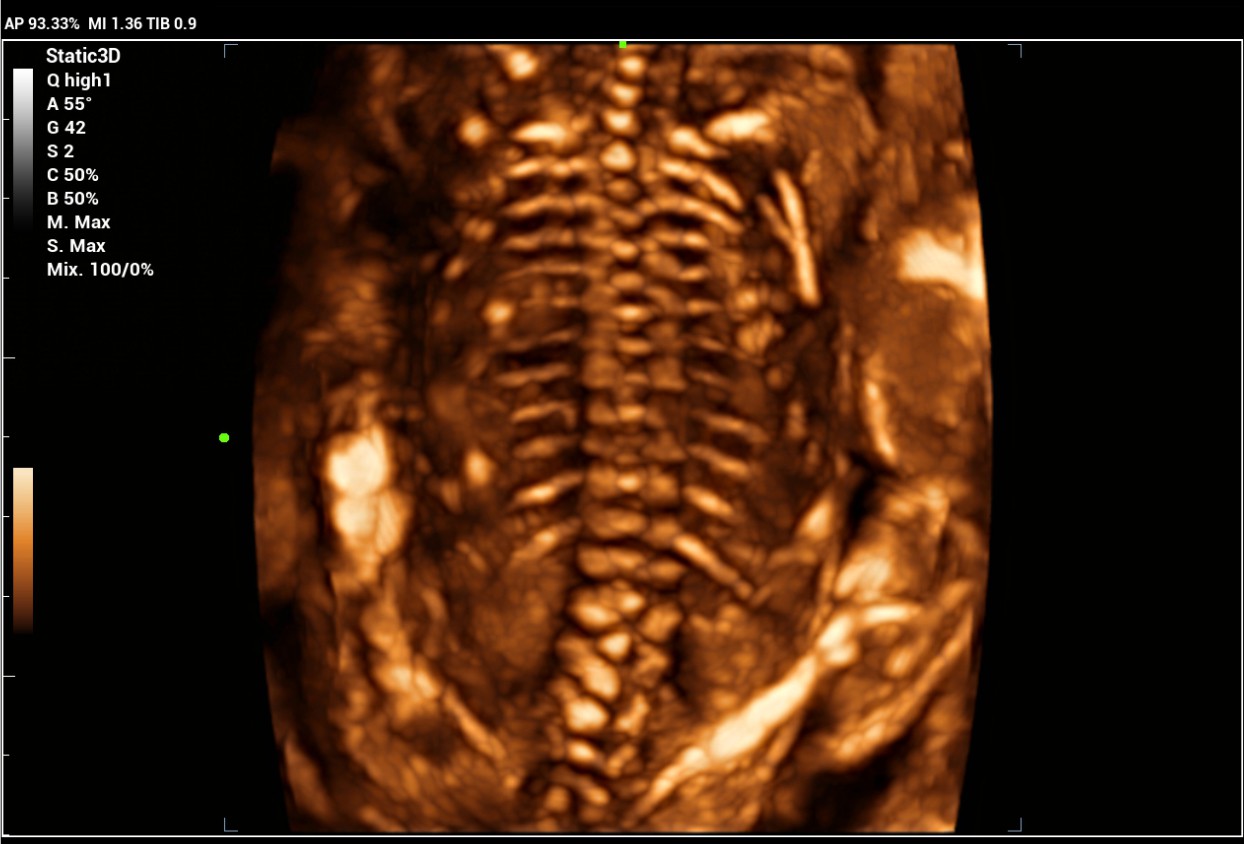

The Consona features new and concrete solutions, that efficiently help you to carry out smooth diagnoses for extensive type of patients. You will find highly powerful tools available on this series to keep you stay ahead in Obstetrics and Gynecology diagnosis.

Image Gallery